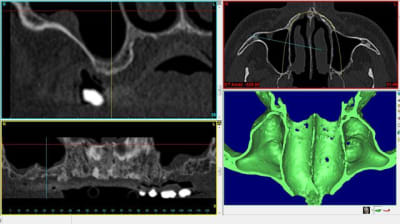

voici 4 scanners montrant la différence de résultat obtenu après un sinus lift.

1 gauche : avant

2 droite : avant

3 droite : après

4 gauche : après

notez surtout qu'à gauche et à droite la consistance est vraiment différente.

à droite : BIO-OS

à gauche :GEN-OS